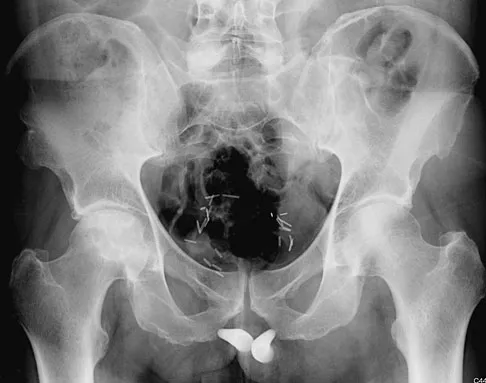

A 61-year-old man reports right hip pain and limited motion after undergoing total hip arthroplasty for posttraumatic arthritis 1 year ago. Figure 6 shows an AP radiograph of the pelvis. To improve motion and relieve pain, management should consist of

Explanation

The patient has symptomatic grade IV Brooker heterotopic ossification. Once the bone has matured, it can be excised. Surgical excision should be combined with postoperative irradiation to avoid recurrence. Pharmacologic and irradiation intervention are not successful beyond the perioperative period unless they are combined with surgical excision of mature heterotopic ossification. Koval KJ (ed): Orthopaedic Knowledge Update 7. Rosemont, IL, American Academy of Orthopaedic Surgeons, 2002, pp 417-451.